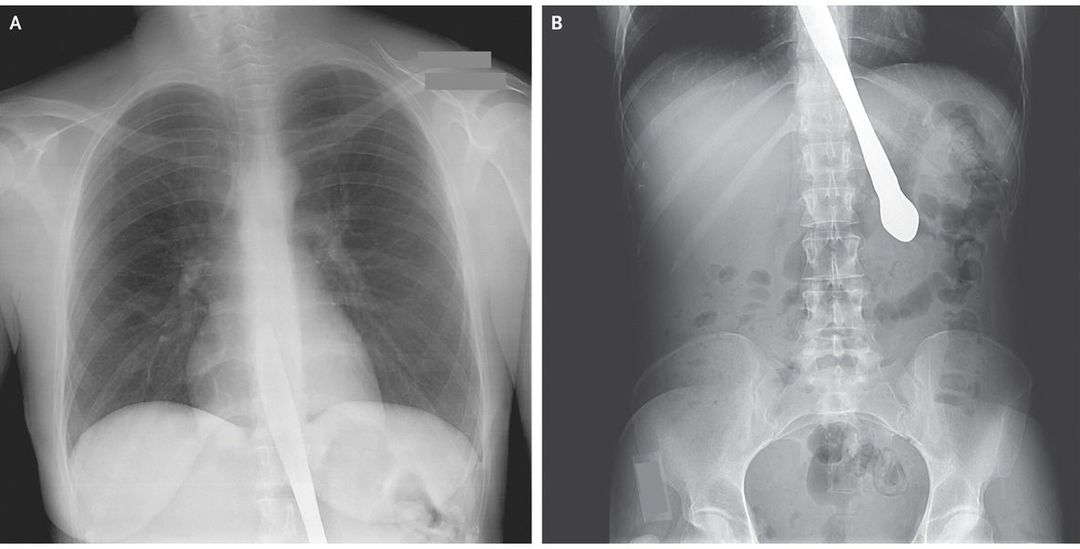

A 30-year-old woman with a history of bulimia presented to the emergency department after swallowing a knife. She inserted the knife into the posterior oropharynx to demonstrate to her companions that she no longer had a gag reflex. When she unexpectedly laughed, the knife migrated into her esophagus, causing chest discomfort and hematemesis. Anteroposterior chest and abdominal radiographs (Panels A and B) revealed a knife within the distal esophagus and proximal stomach, without evidence of pneumothorax, pneumomediastinum, or pneumoperitoneum. A rigid esophagogastroduodenoscopy was performed to remove the knife. The esophagus and stomach otherwise appeared grossly normal. A swallowing study showed no extravasation of contrast material from the upper gastrointestinal tract, and the patient subsequently resumed eating without complications. Her husband later disclosed that 4 years earlier she had swallowed a knife that required surgical removal with exploratory laparotomy. Consultation with a psychiatrist was recommended, and the patient was later transferred to an inpatient psychiatric unit.